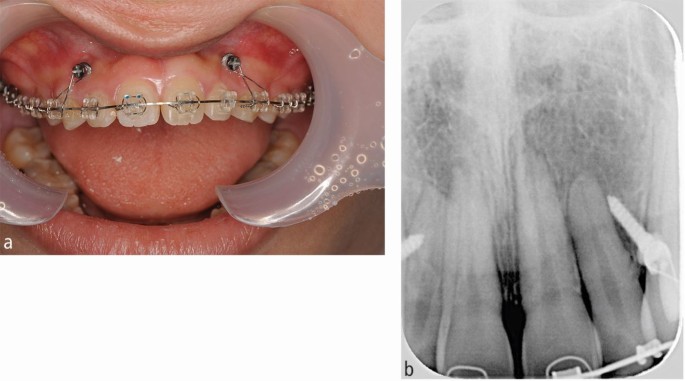

For orthodontic treatment, 0.018-inch standard edgewise brackets were bonded on the maxillary teeth. Two self-drilling TADs (diameter, 1.6 mm; length, 8 mm; Dual Top Auto Screw; Jeil Medical Corp, South Korea) were inserted into the buccal alveolar bone between the maxillary lateral incisors and canines to intrude the maxillary anterior teeth using an elastic chain. Before completion of opening the bite, positive crown torque of the upper incisors was achieved by torque moment generated with intruded force (Fig. 2A). After opening the bite, brackets were bonded on the mandibular teeth to create space between mandibular right central incisor and canine. However, after 12 months of intrusion, the crown of the maxillary right central incisor showed grey discoloration and a negative response to electric pulp tests (Fig. 2B). Furthermore, the patient reported severe spontaneous pain only in this tooth two days before visiting our clinic. However, no significant radiographic change was observed around the root apex of the maxillary right central incisor. Notably, moderate apical root resorption was observed in the maxillary right lateral incisor by the dental x-ray (Fig. 2C). From these symptoms, we thought traumatic pulp injury occurred on the right central incisor. Therefore, we removed the orthodontic force on the maxillary incisors with passive wire ligations between TADs and the upper canines, and 60 mg of loxoprofen sodium was administered three times a day for seven days. No more intrusion force to the upper incisors was applied because opening the bite had been completed. Six months after stopping orthodontic treatment, resolution of the crown discoloration was observed and the response to electric pulp testing was restored (Fig. 3A). Periapical radiography revealed a distinct radiolucency at the root apex (Fig. 3B). Two years after initiation of orthodontic treatment, the patient's gummy smile and overbite were corrected with a good intercuspal relationship. The missing mandibular right lateral incisor was replaced by direct bonding (Fig. 4A, Fig. 4B). Follow-up at four years after beginning of retention revealed stable smile aesthetics and tooth positions (Fig. 4C, Fig. 4D). Periapical radiographs showed marked root canal obliteration in the maxillary right central incisor and remodelling of the root apex in the maxillary right lateral incisor (Fig. 4E). The wire sequence used in this case is shown in Table 1.

Studies describing TAB during orthodontic treatment are scarce,9 and the mechanism of TAB is not completely clarified. However, orthodontic tooth movement likely induces non-infectious inflammation of the apical pulp tissue. McDonald reported that continuous orthodontic tipping forces caused a decrease in the pulpal blood flow.1 Miura showed that pulp necrosis occurred under continuous heavy orthodontic forces due to rupture of blood vessels in the root apex.2 Moreover, the pulp tissue in the root apex plays an essential role in the incidence of inflammatory periapical root resorption during orthodontic tooth movement.10 Tsukiboshi suggested the following mechanism for TAB.11 Immediately after trauma, the apical blood vessels rupture, and ischemic pulp necrosis is induced. Next, pulp necrosis causes non-infectious inflammation in the apical pulp tissue with periapical alveolar bone and root resorption. Several months after trauma, the foramen of the root apex expands because of inflammatory apical root resorption, followed by recovery of the periapical blood vessels. Finally, the pulp tissue shows obliteration several years after trauma. This sequence of pulp healing was distinctly observed in our patient. Interestingly, TAB in the maxillary right central incisor and mild apical root resorption in the maxillary right lateral incisor occurred spontaneously in our patient. These findings strongly suggested that both TAB and apical root resorption during orthodontic tooth movement are caused by the same inflammatory periapical reaction. Similar inflammatory reactions were observed in the root apex during orthodontic tooth movement in animal studies. Yamamoto showed that the expression of interleukin-1β, receptor activator of nuclear factor kappa-B ligand, tumour necrosis factor-α, and macrophage colony-stimulating factor in the apical pulp tissue increased after orthodontic tooth movement in rats.8 Interestingly, these inflammatory reactions decreased with loxoprofen or acetaminophen administration.8,12 Ersahan reported that pulpal blood flow decrease during orthodontic tooth movement in older patients was more severe and persisted for a longer duration than that in younger patients.13 Similarly, Andreasen reported that TAB is more likely to occur in patients aged <20 years.5 Considering these findings, we prescribed 60 mg of loxoprofen sodium three times a day for seven days and removed the orthodontic force immediately after the appearance of crown discoloration in the maxillary right central incisor to improve TAB. Consequently, the crown colour improved and sensitivity to electric pulp testing returned after six months. The findings in this case suggest that removal of orthodontic force is the first-line treatment to improve TAB during orthodontic treatment, and NSAIDs may help improve non-infectious pulpal inflammation, even in older patients.